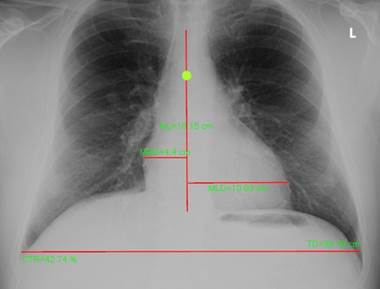

CTR

Cardiothoracic Ratio: click & drag mouse to draw line down spine, then repeat to draw perpendicular lines for the MLD, MRD, and TD.

CTR measurement

The four lines draw for the CTR measure need to be drawn in the following order:

1.      ML = midline of the spine

2.      MLD = maximum transverse diameter of the left side of the heart, which is a line drawn from the midline of the spine to the most distant point of the left cardiac margin

3.      MRD = maximum transverse diameter of the right side of the heart, which is a line drawn from the midline of the spine to the most distant point of the right cardiac margin.

4.      DT = diameter thorax (also referred to as ID = Internal diameter) greatest internal diameter of the thorax )

An example of the CTR measurement is shown below:

Once all four lines have been drawn, the CTR will be calculated and displayed on the image using the following formula: CTR = (MRD + MLD)/ID